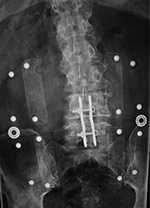

Posterior spinal fusion apparatus |

Shown are pedicle screws and rods on each side, two crosslinks (at L4 and S1), and intervertebral disk spacers at L4-5. |